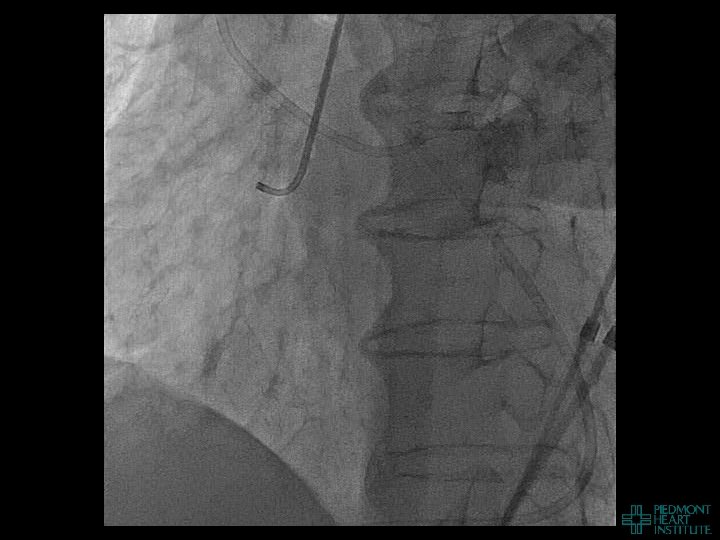

Day 2 Stable overnight No further pericardial drainage Echo shows no recurrence of effusion

Day 2 Stable overnight No further pericardial drainage Echo shows no recurrence of effusion In ICU, pericardial pigtail catheter pulled…. . Within 5 minutes, systolic blood pressure drops to <80 and bedside echo confirms recurrence of effusion Emergency pericardiocentesis draws off 650 cc immediately followed by continuous drainage of blood